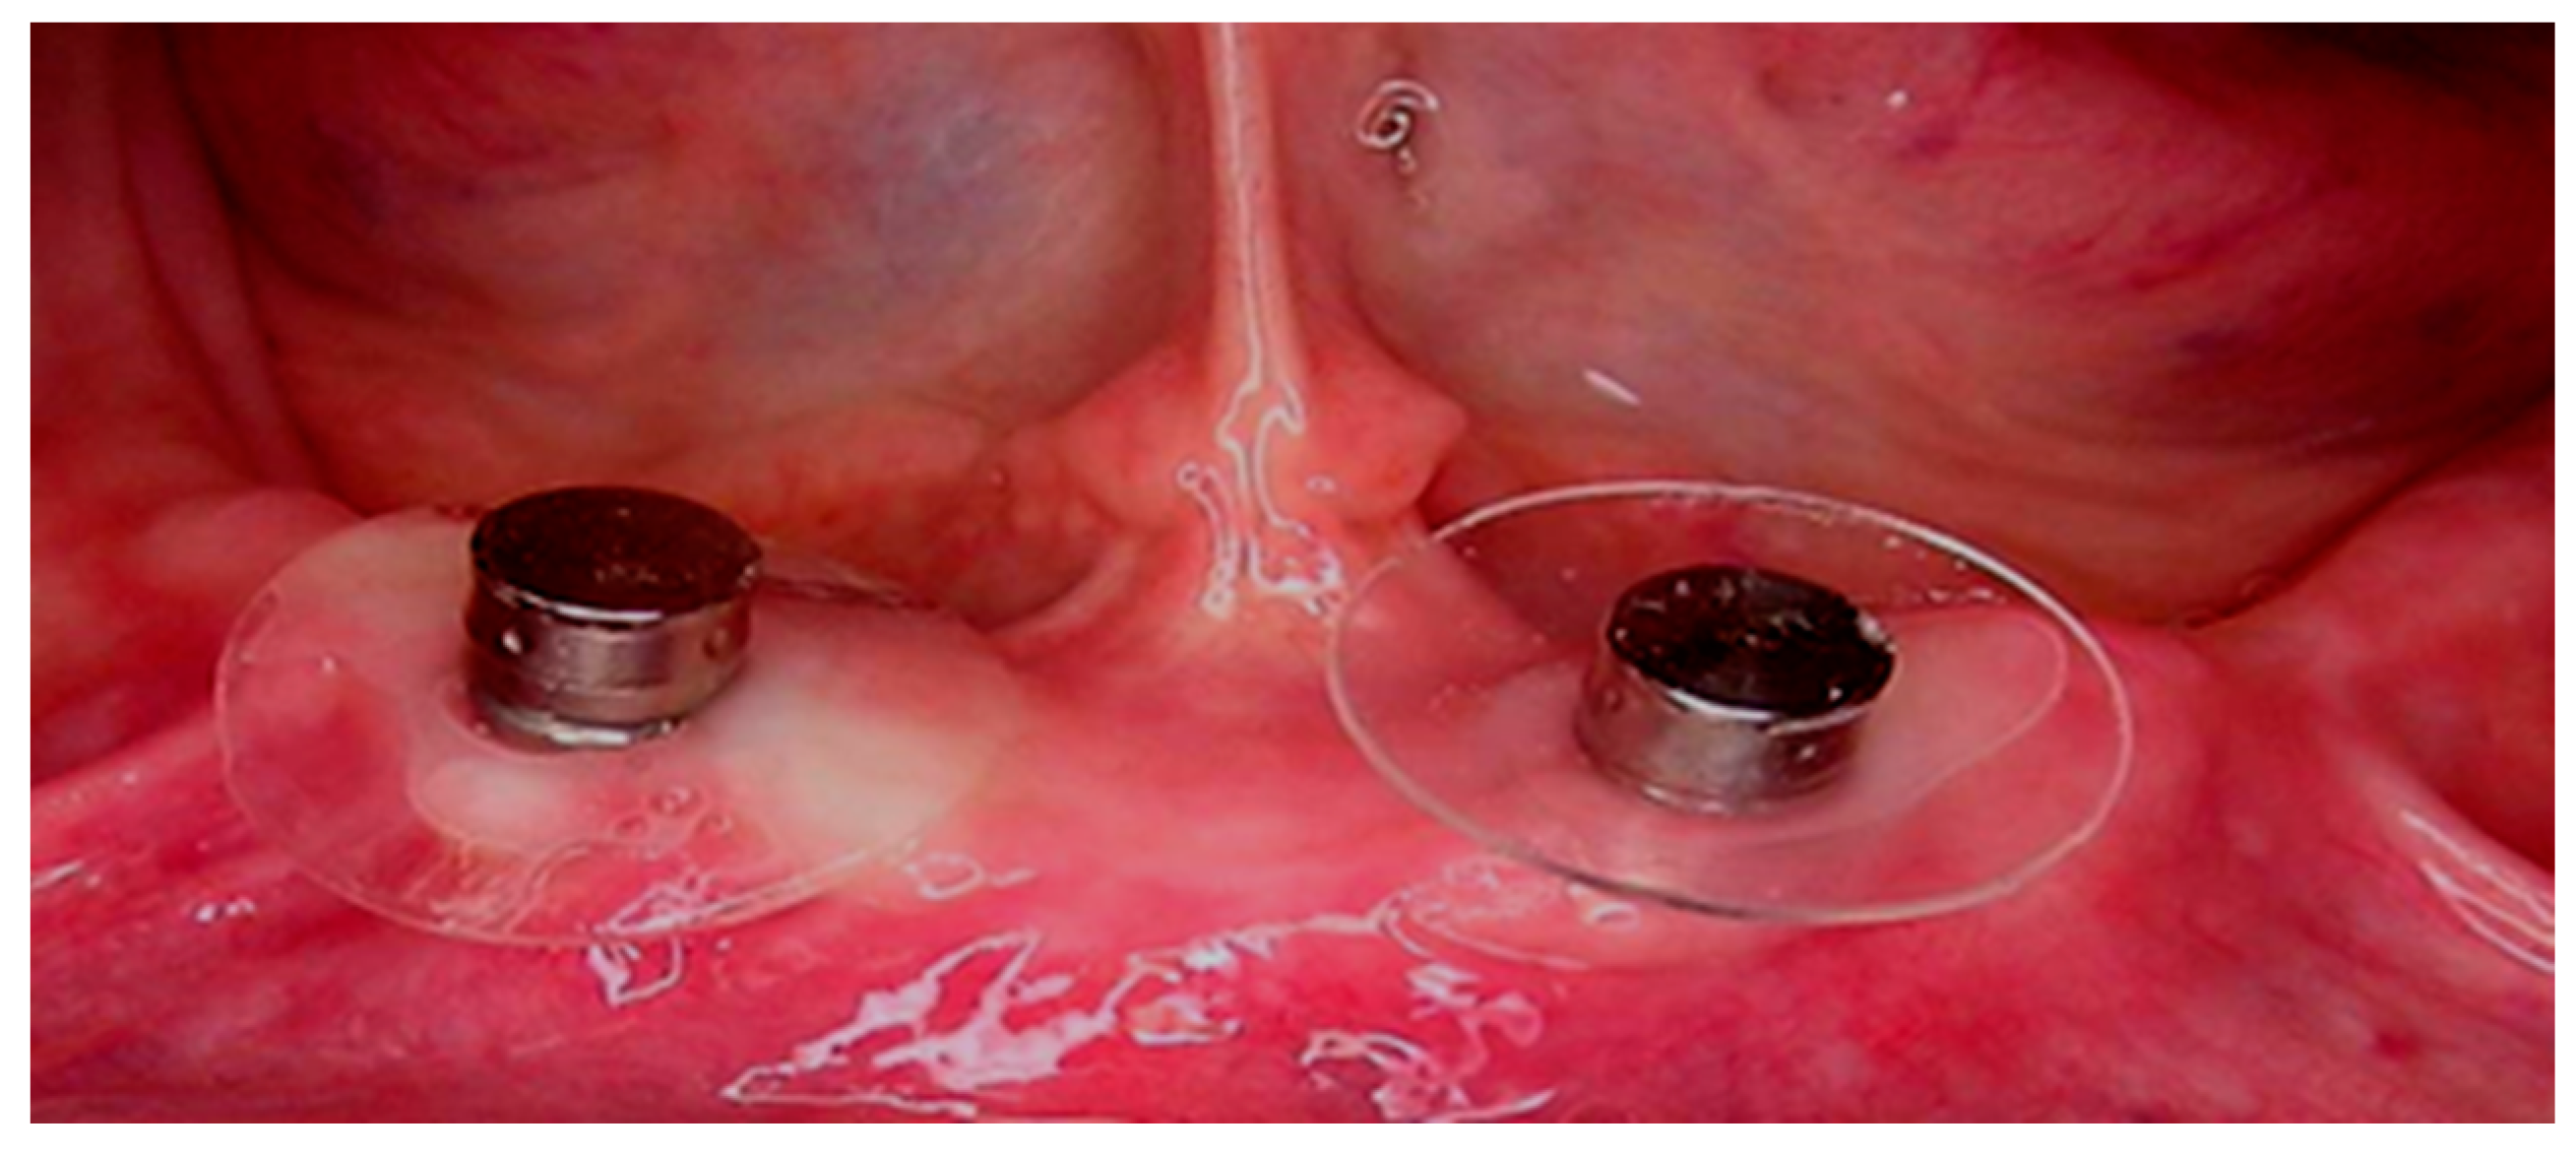

2.3. Surgical Treatment

2.4. Prosthetic Treatment